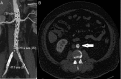

We present a case of a 67-year-old man who was an active smoker, with a clinical history of ischaemic cardiopathy, hypertension, who presented to the emergency room with hoarseness of voice of 2 weeks duration. No other neurological or cardiorespiratory symptoms were found. Physical examination revealed an aortic regurgitation murmur with radial pulse difference between the upper limbs and femoral pulse difference on lower limbs. Laryngoscopy examination revealed a left vocal cord paralysis in the paramedian position, without signs of malignancy. Thoracoabdominal CT angiography was performed to rule out an aortic dissection. CT revealed a dissection in the descending thoracic aortic arch and abdominal aorta. Cardiovascular surgery was consulted and decided to place endoprosthesis at the thoracic and abdominal aortic area. Hoarseness eventually resolved during the following weeks. Ortner's syndrome is described as hoarseness of voice caused by compression of the left recurrent laryngeal nerve of cardiovascular origin.